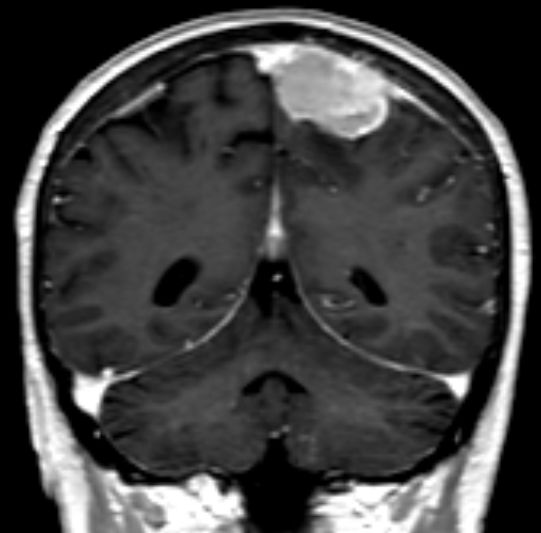

| Meningeom frontal |

59-jähriger Patient, der wegen AV-Block in die Kardiologie eingeliefert wurde. Das CT zeigt einen hirninvasiven Tumor, der die Mittellinie überschreitet. Postoperativ ergab sich ein Meningeom 2. Grades. | . |